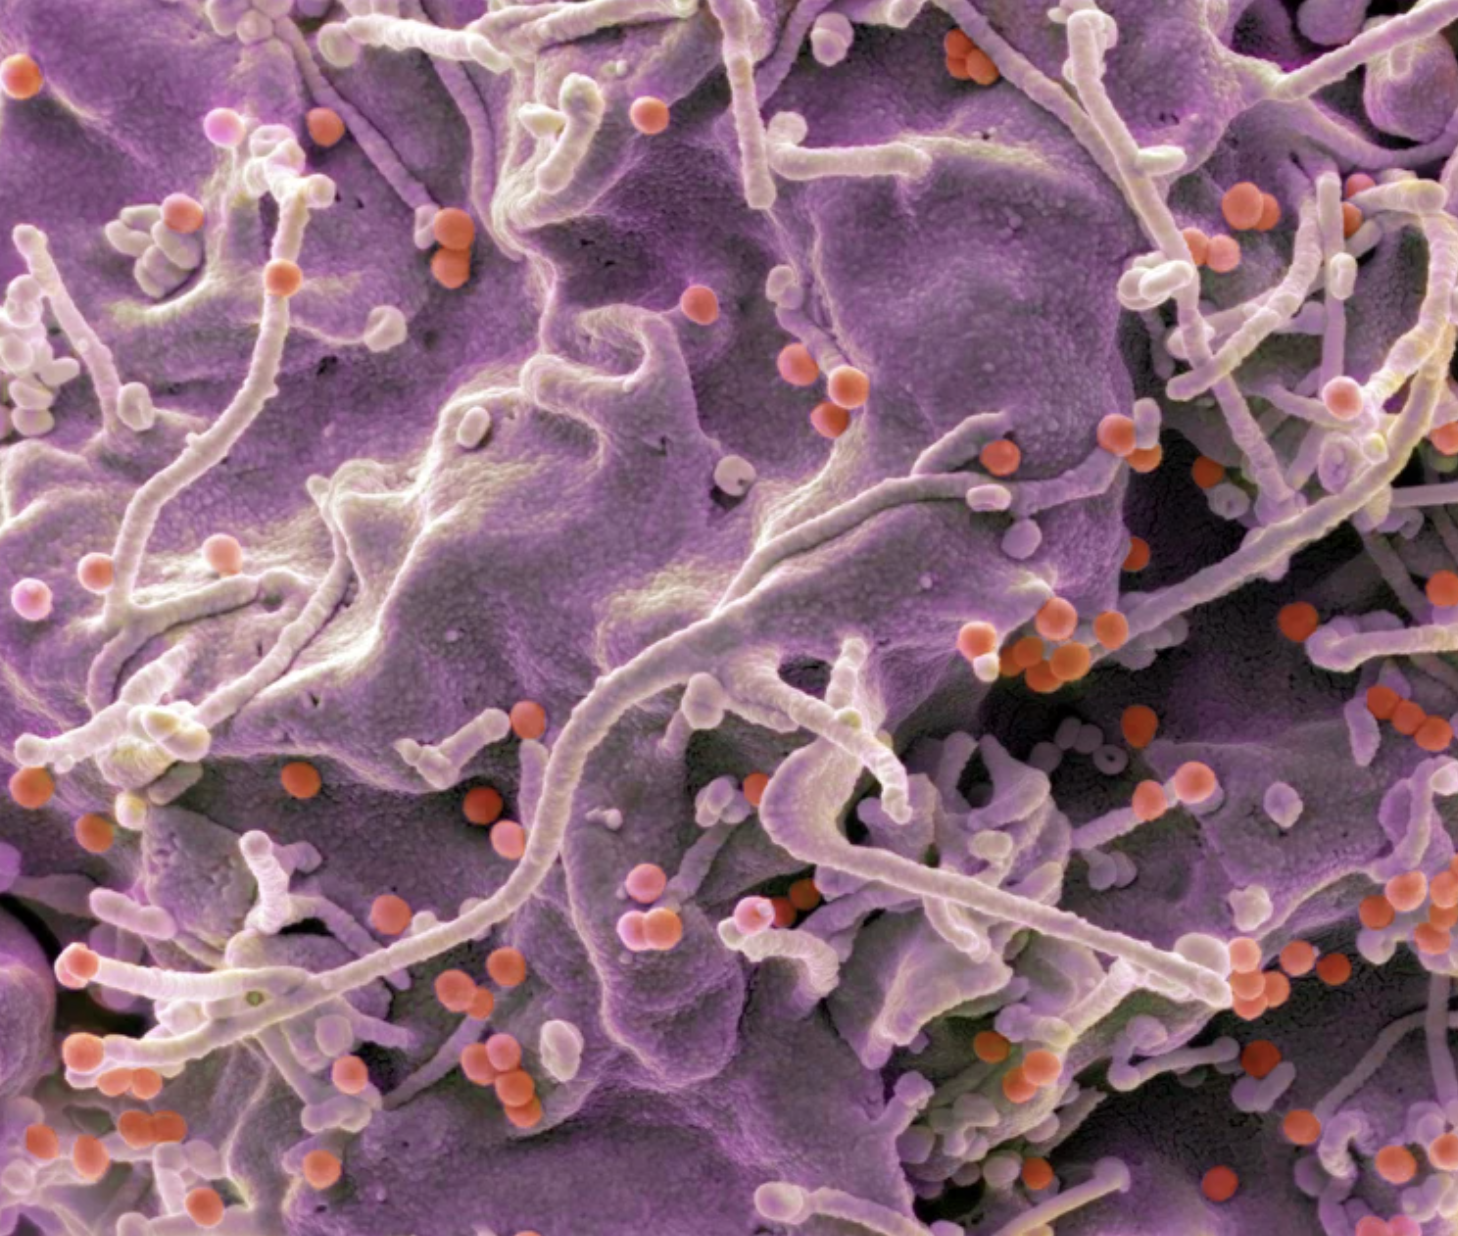

சமீபத்தில் உருவாக்கப் பட்ட mRNA தடுப்பூசி மூலம் எயிட்ஸ் நோய்க்கான HIV கிருமிக்கு எதிராக ஸ்திரமான நோய் எதிர்ப்பு சக்தியை நோயாளிகளிடம் ஏற்ப்டுத்தியுள்ளது. ஆரம்ப கட்ட சோதனைகளில் மனித உடலுக்கு பாதிப்பை ஏற்படுத்தும் வைரஸ் புரதங்களுக்கு எதிரான நுண்ணுயிர் எதிர்ப்பை (Antibodies) ஐ ஏற்படுத்தும் இரு தடுப்பூசிகள் போடப் பட்ட போது அதில் 80% வீதமான பங்குபற்றுபவர்களுக்கு நல்ல மாற்றம் ஏற்பட்டது. இந்த ஒரு தடுப்பூசிகளுமே மனிதக் கலங்களின் அடிப்படைக் கூறுகளில் ஒன்றான mRNA தொழிநுட்பத்தால் உருவாக்கப்…